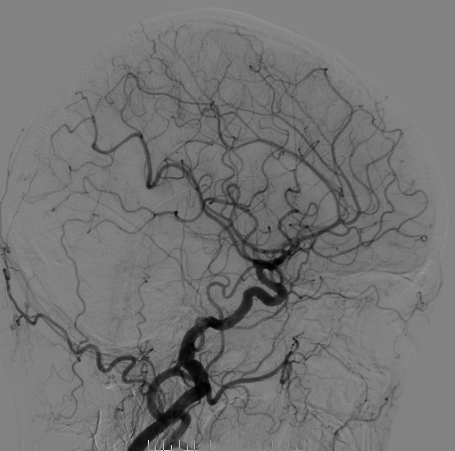

脑血管造影

右侧颈总造影:右侧大脑中动脉瘤

右侧椎动脉硬膜外V2、V3段梭形扩张,前向血流通畅。